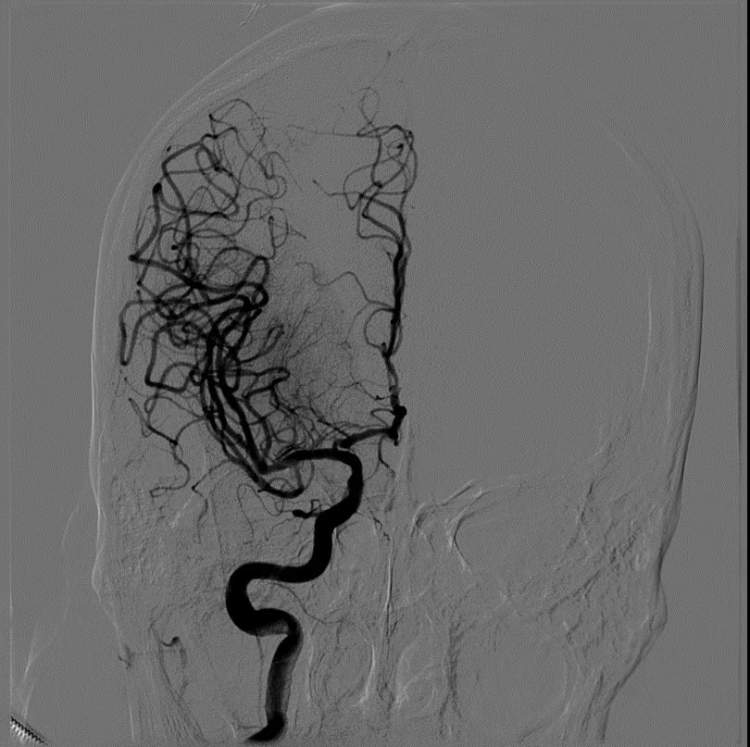

电话就是命令,新华医院“卒中绿色通道”立即启动,神经外科荆朝晖、李宾副主任医师、张新博士,5分钟左右赶到导管室,DSA造影证实放大叔右侧大脑中动脉有血栓堵塞。

考虑到方大叔发病急、症状重,且发病时间在30分钟内,神经外科卒中团队兵分两路,一队与家属积极沟通急诊取栓手术的必要性和风险度,签署知情同意书;另一队与心血管内科介入团队紧密合作,联系麻醉科孙瑗副主任医师紧急支援,从诊断-插管-麻醉-治疗-开通,50分钟,取栓手术一气呵成。

手术后,方大叔闭塞的血管开通了,意识障碍改善了,肢体活动较前明显好转,复查头颅CT未见明显异常,安全返回病房。在新华医院多学科团队成员的通力协作下,方大叔转危为安,避免了脑梗后偏瘫失语等并发症的发生。